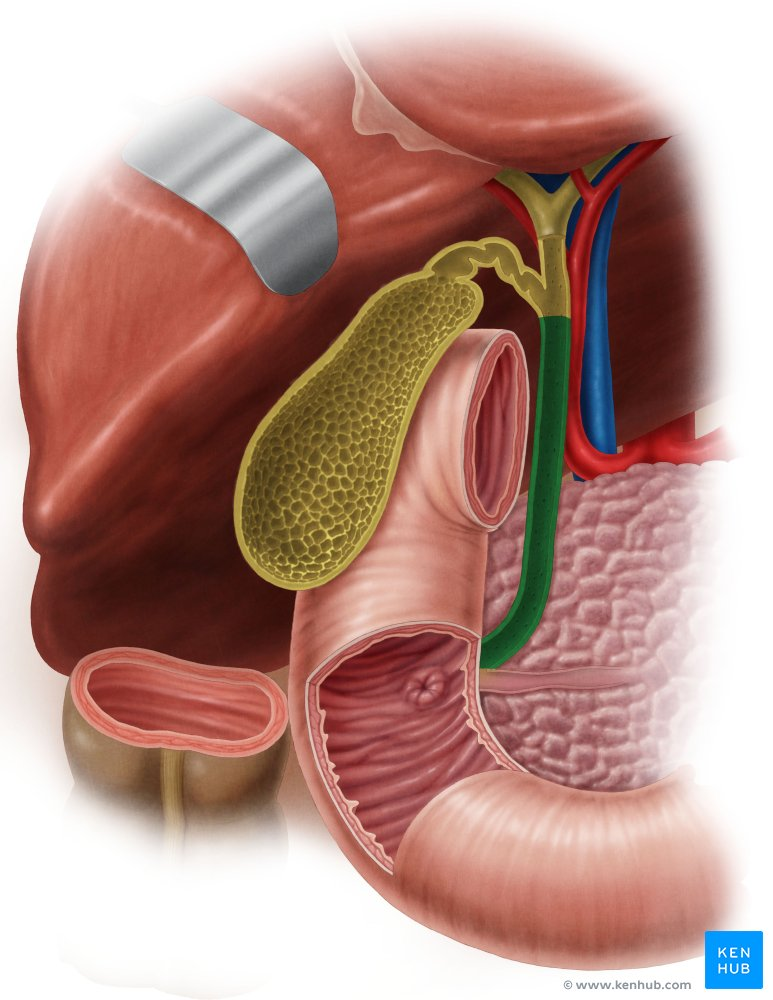

Pancreatic Duct

A duct that carries digestive enzymes produced by the pancreas to the duodenum. It typically joins with the bile duct before entering the duodenum.

Bile duct

A duct that carries bile produced by the liver and stored in the gallbladder to the duodenum, where it aids in the digestion of fats.

Major Duodenal Papilla

An opening in the wall of the duodenum where the common bile duct and the pancreatic duct typically enter to deliver bile and pancreatic enzymes.

Gallbladder

A small, pear-shaped organ located beneath the liver that stores and concentrates bile produced by the liver.

Right Hepatic Duct

A duct that carries bile produced by the right lobe of the liver.

Left Hepatic Duct

A duct that carries bile produced by the left lobe of the liver.

Common Hepatic Duct

The duct formed by the union of the right and left hepatic ducts, which carries bile away from the liver.

Cystic Duct

The duct that connects the gallbladder to the common hepatic duct, allowing bile to enter and exit the gallbladder.

Hepatic Artery

A branch of the celiac artery that supplies oxygenated blood to the liver.

Hepatic Portal Vein

A large vein that carries deoxygenated but nutrient-rich blood from the digestive organs (stomach, intestines, spleen, pancreas) to the liver for processing.

Pancreatic Duct / Duct of Wirsung

The main duct that runs through the length of the pancreas, collecting digestive enzymes from the pancreatic cells and transporting them to the duodenum.

Accessory Pancreatic Duct / Duct of Santorini

A smaller pancreatic duct that branches off the main pancreatic duct and may also empty into the duodenum, usually superior to the major duodenal papilla.

Hepatopancreatic Ampulla / Ampulla of Vater

A dilated chamber formed by the joining of the common bile duct and the pancreatic duct before they enter the duodenum.

Sphincter of Hepatopancreatic Ampulla / Sphincter of Oddi

A muscular valve that surrounds the hepatopancreatic ampulla and controls the flow of bile and pancreatic juice into the duodenum.

Major Duodenal Papilla

The raised opening in the wall of the duodenum where the hepatopancreatic ampulla typically empties its contents.

Mucosa of Duodenum

The inner lining of the duodenum, which contains specialized cells for absorption and secretion.